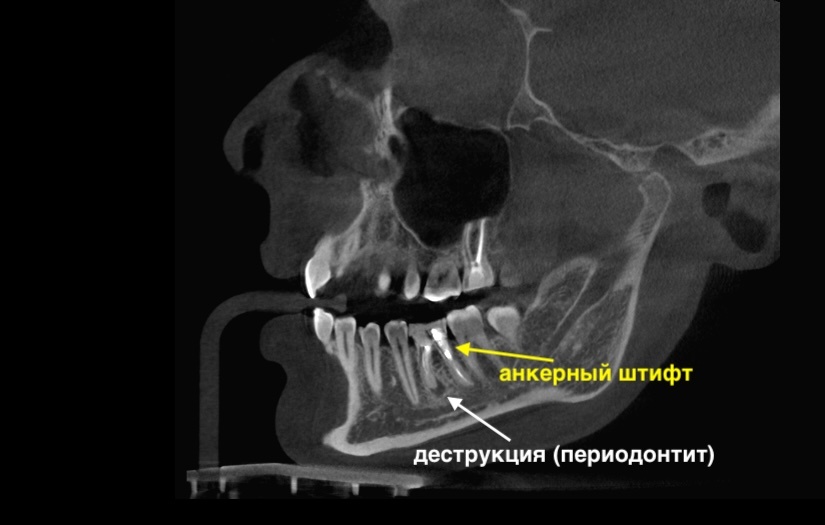

Зуб справа (4.6):

Зуб 4.6

В дистальном корне стоит анкерный штифт, в медиальном - периапикально очаг воспаления. Каналы уже не пощадила эта жизнь, если пытаться перелечить, после обработки от корней мало что останется.